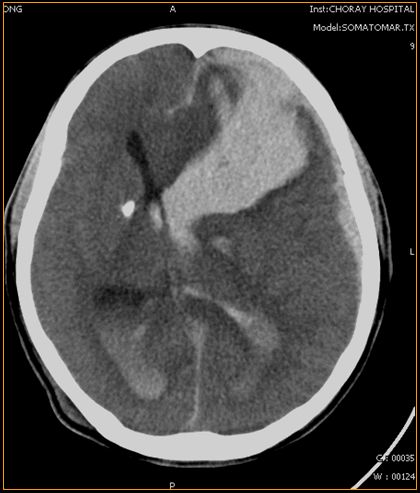

Xuất huyết não và não thất

Xuất huyết não thất được coi như một hiện tượng thứ phát do chảy máu não vỡ hoặc chảy máu nhu mô não vào khoang não thất. Đây là một trong những bệnh lý gây tử vong cao. Chẩn đoán và điều trị sớm bệnh sẽ giúp nâng cao cơ hội sống cho bệnh nhân. Để hiểu rõ hơn về hội chứng nguy hiểm này, mời các bạn tham khảo bài viết dưới đây!